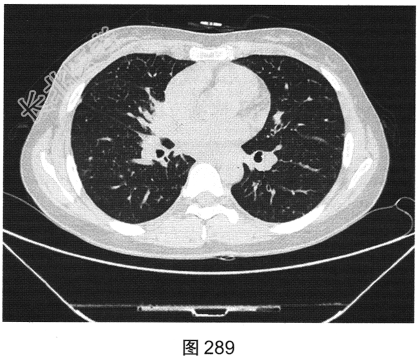

- [材料题] 患者女性,43岁,因“确诊肺低分化腺癌1周”就诊。患者于2014年11月无明显诱因出现咳嗽、咳痰,无胸闷胸痛,无咯血,无发热、乏力、体重减轻等。自服中药治疗,止咳效果尚可。2015年4月22日在山海关人民医院行胸部CT:显示①慢性支气管炎继发感染,建议结合临床及病史考虑;②右侧中间段支气管及中叶支气管壁增厚、管腔狭窄伴右肺中叶阻塞性肺不张,右侧肺门及纵隔多发淋巴结增大,建议增强扫描。后补做增强CT:右肺中叶支气管增厚,管腔狭窄伴阻塞性肺不张,考虑右侧中心型肺癌伴纵隔多发淋巴结增大,建议行支气管镜检查。支气管镜取活检病理:示低分化腺(右肺中叶)癌,建议做免疫组织化学检测,以进一步明确诊断。于北京肿瘤医院行PET/CT检查:①右肺中叶支气管起始部位高代谢结节,符合中心型肺癌表现;右肺中叶部位阻塞性不张,不张肺内高代谢结节,倾向肺内转移;双肺多发转移结节;双锁骨上区、左胸肌间、纵隔及双肺门多发淋巴结转移。②脑部未见明显高代谢征象,建议行增强MRI检查。③双叶甲状腺炎性或非特异性摄取,建议行B超及甲状腺功能检查。患者精神状态良好,体力、食欲、睡眠均正常,体重无明显变化,大便、排尿正常,为进一步检查及治疗,门诊以“肺癌”收入院。2015年5月5日在我院行CT检查,如图288~图295所示。